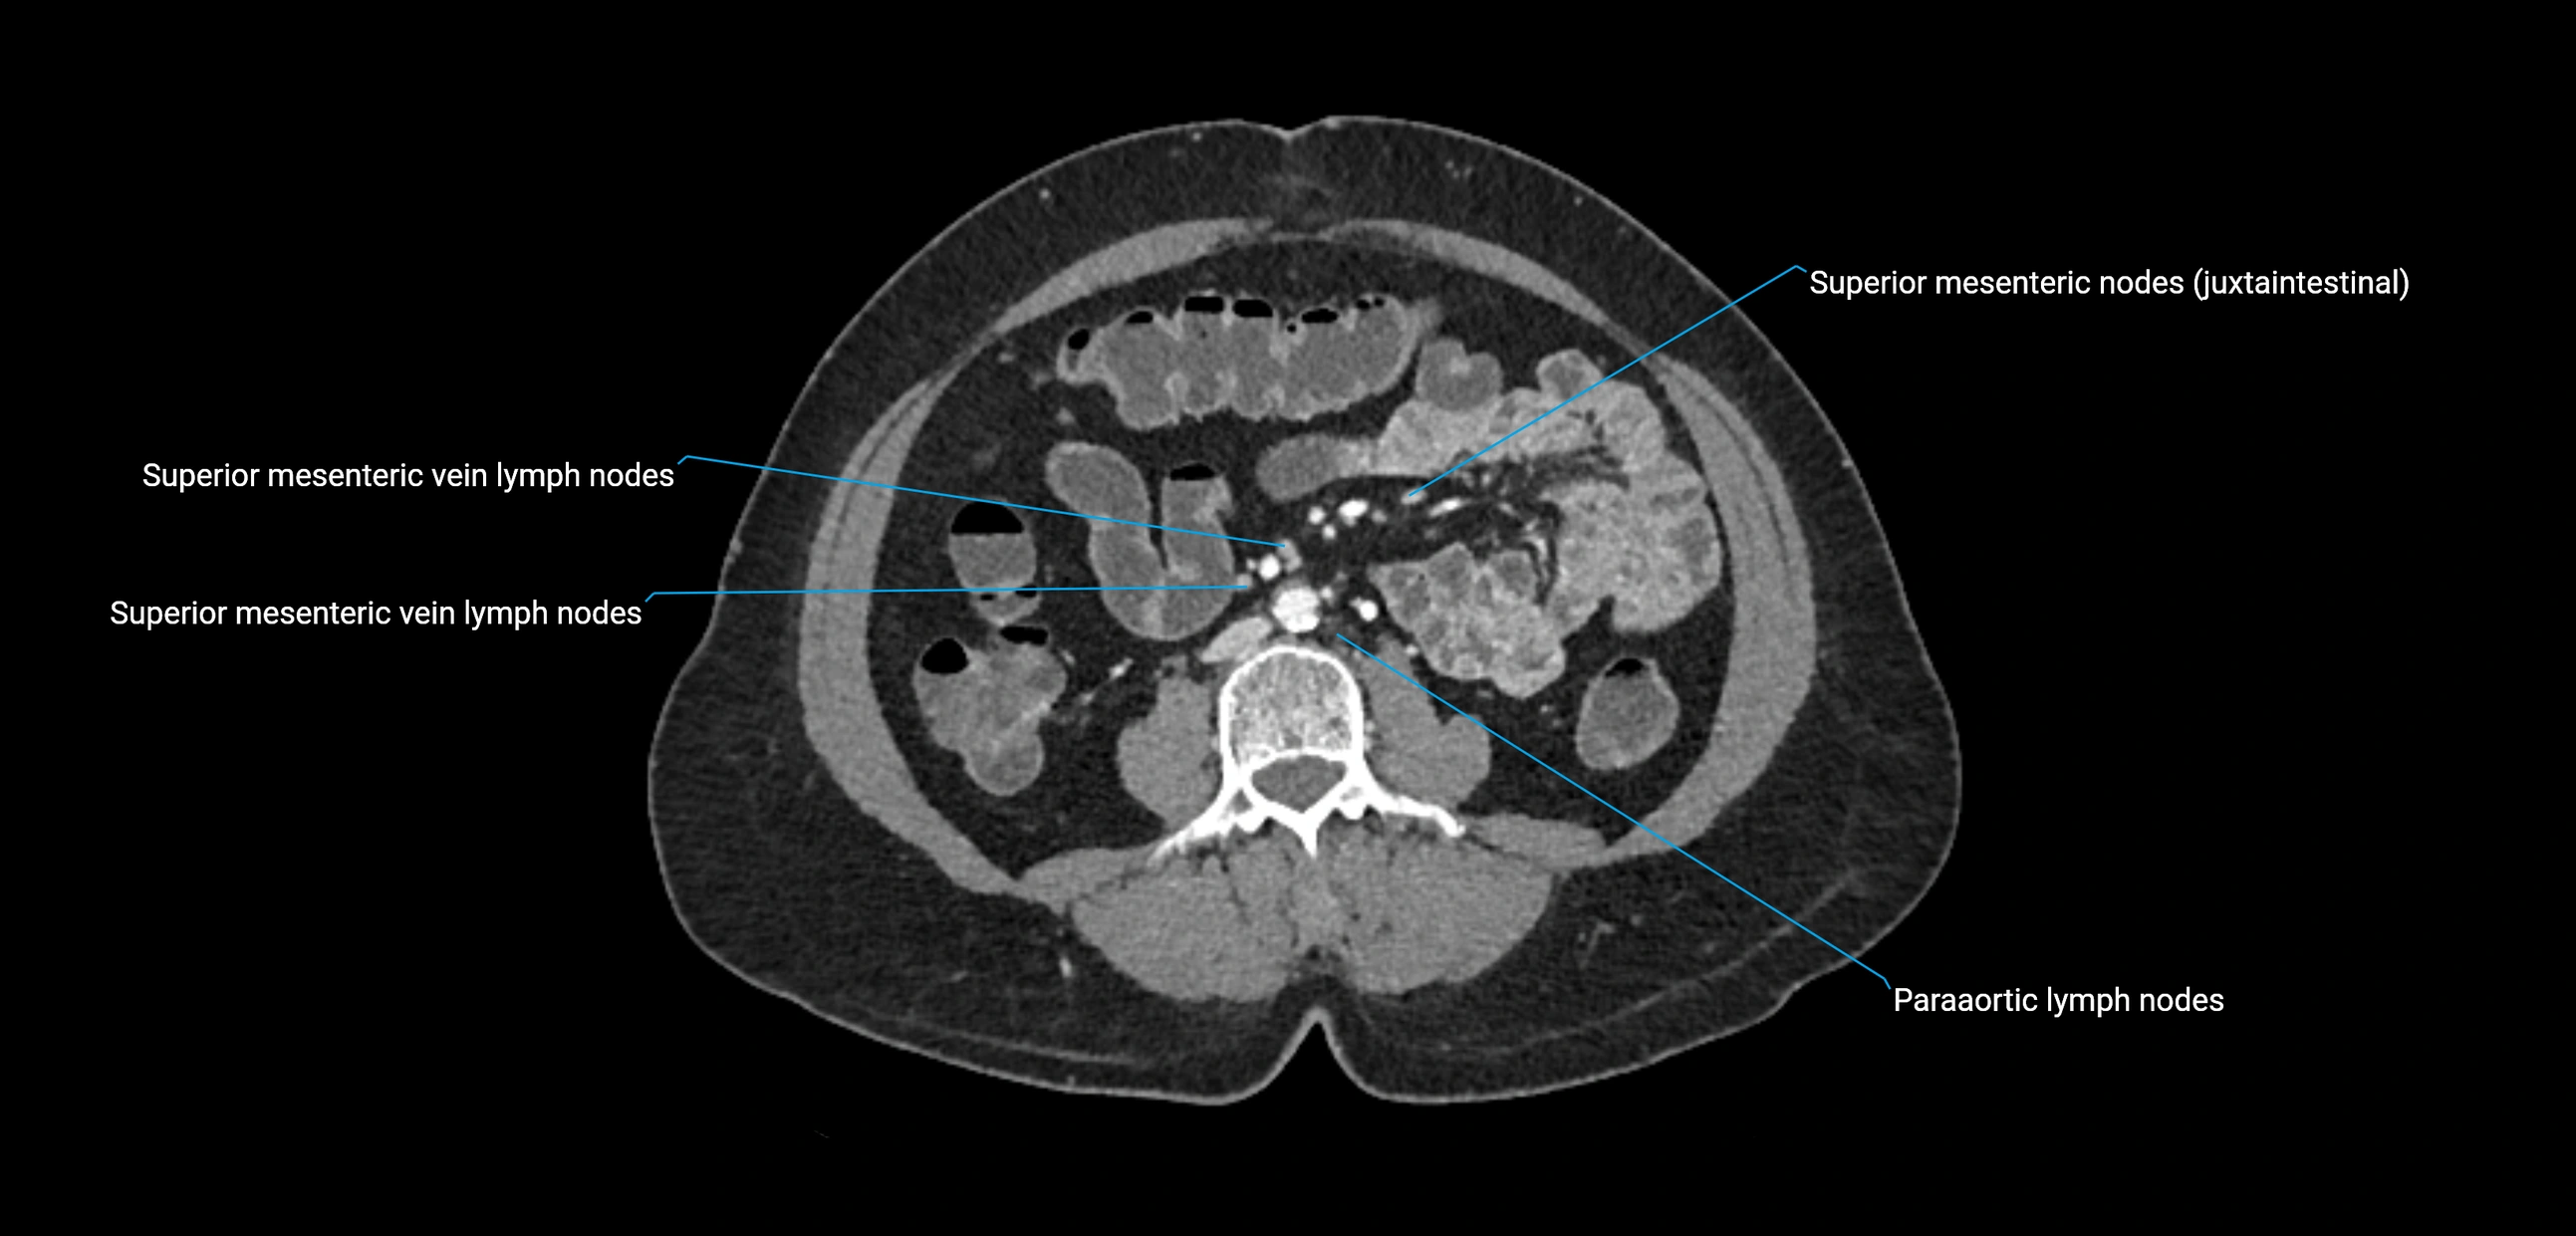

CT image

image